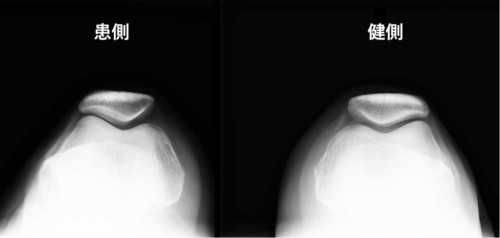

スカイライン像(膝蓋骨軸位):膝蓋骨が外側へ偏位/傾斜。→ PF関節の外側コンフリクトが起きやすい。